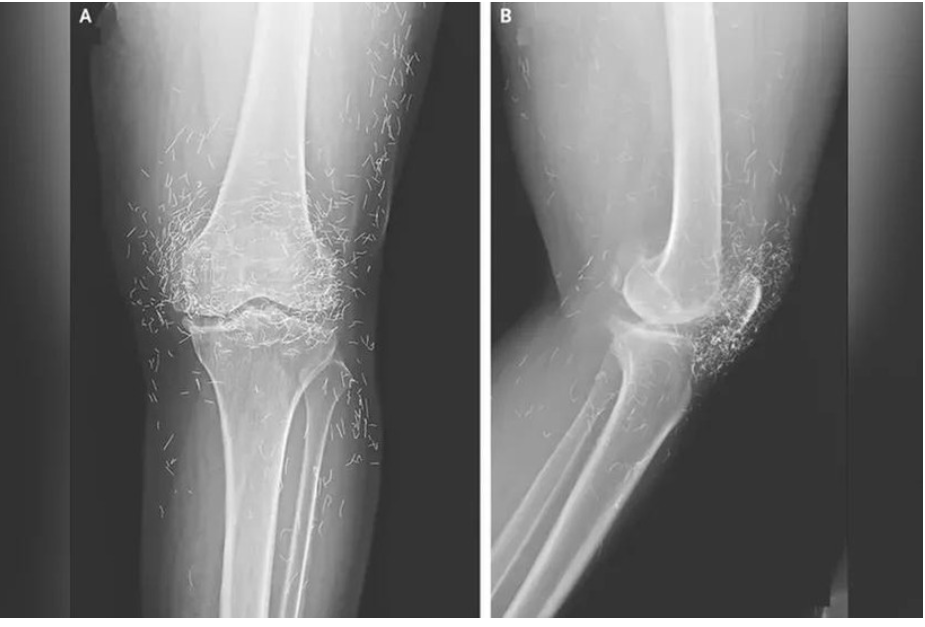

Ảnh chụp X-quang cho thấy hàng trăm sợi chỉ vàng trong đầu gối của nữ bệnh nhân. Ảnh: OddCentral.

Kết quả chụp X-quang cho thấy tình trạng dày và cứng bất thường ở phần xương chày trong, sự phát triển của gai xương quanh đầu gối – những triệu chứng điển hình của thoái hóa khớp – cùng với hàng trăm sợi chỉ vàng li ti được cấy vào các mô quanh khớp.